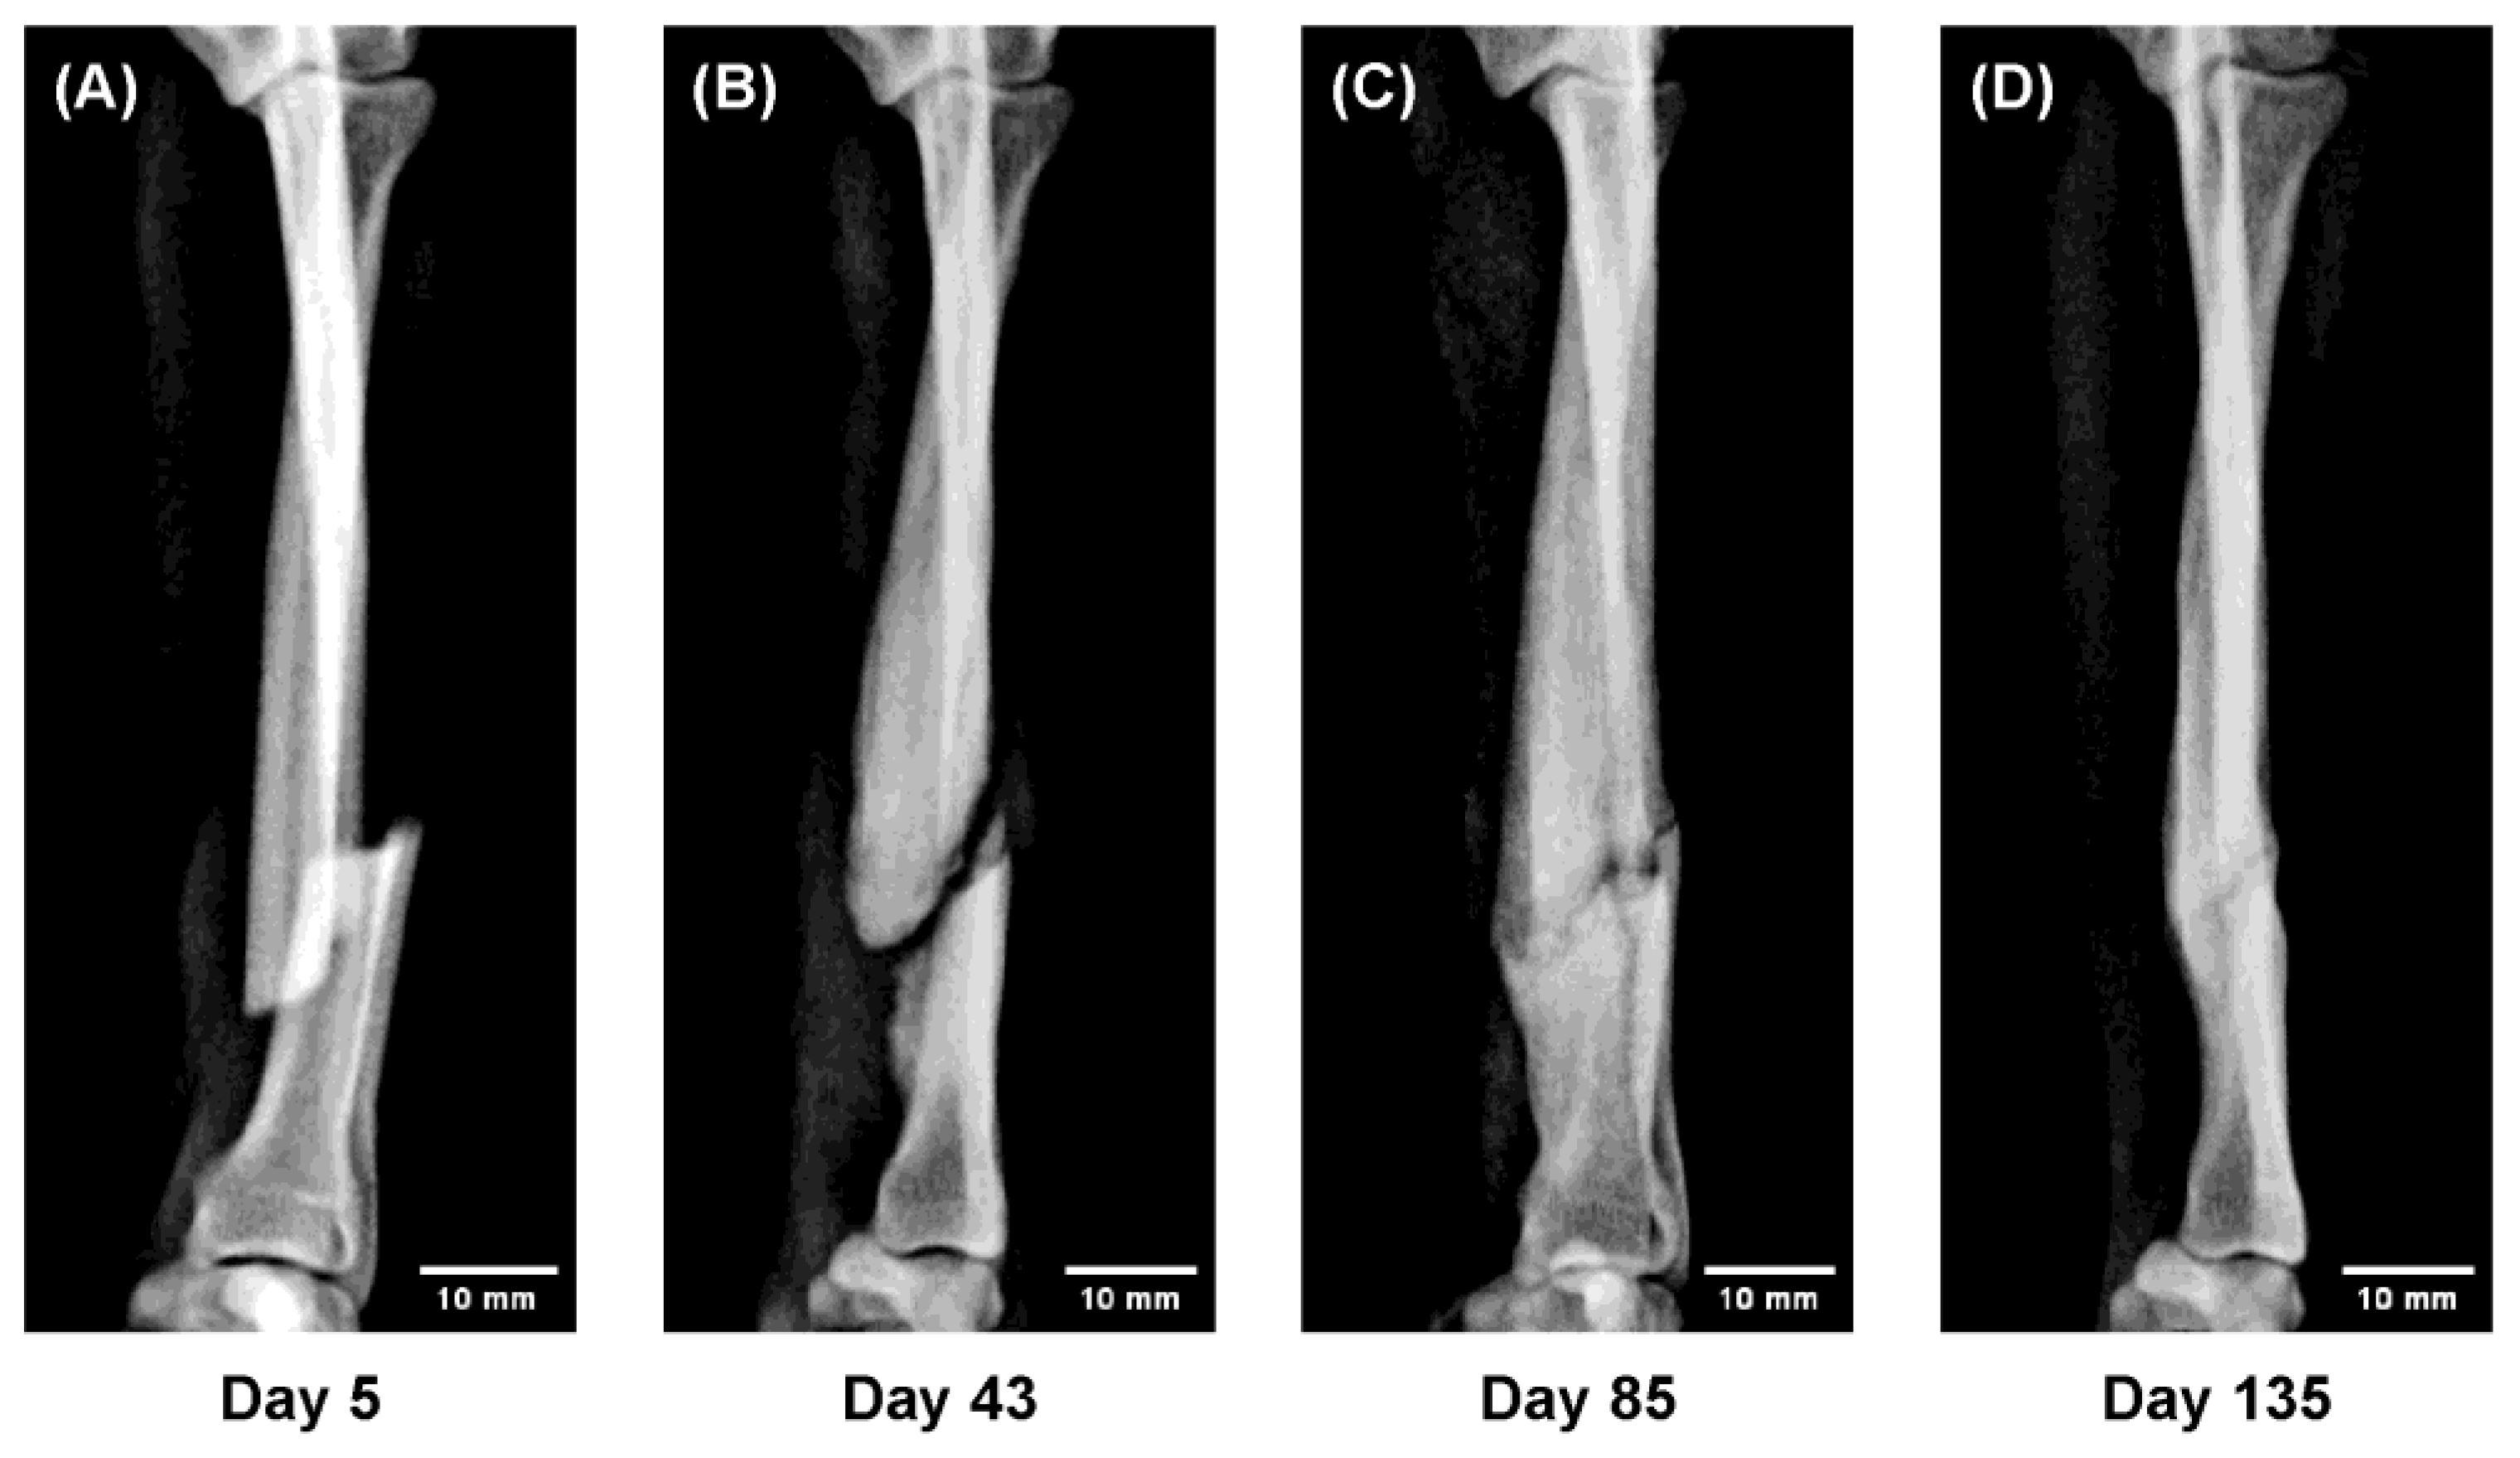

Figure 6.

Sequential radiographs showing gradual realignment of displaced fragments under functional loading (“Slide-Healing”). The progressive correction of malalignment through load-guided remodeling demonstrates how physiological mechanical stimuli can direct bone regeneration—a principle central to regenerative medicine. (A) Day 5 after injury; temporary immobilization performed; 3D cast applied on Day 10. (B) Day 43: abundant callus with gradual realignment of fragments. (C) Day 85: bony union confirmed; cast removed on Day 100. (D) Day 135: remodeling with restored alignment and normal bone thickness.

Figure 6. In a 9 month-old Toy Poodle with a markedly displaced fracture, gradual realignment of the fracture fragments was observed under weight-bearing conditions during 3D cast fixation.

Ordinarily, allowing ambulation in such cases results in bending deformity at the fracture site due to axial loading; however, the 3D cast maintained a physiological stress distribution, leading to a self-correcting realignment of the fragments over time. This spontaneous alignment under functional loading, accompanied by abundant callus formation ensuring stability, was defined as “Slide-Healing.”